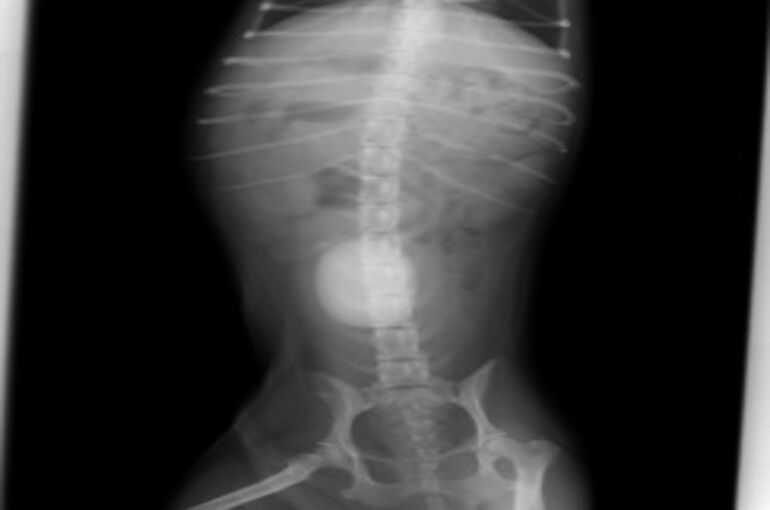

膀胱結石に間違いないと判断し、レントゲンを撮りました。

それが下の写真です。かなり大きな膀胱結石が存在していました。

ここまで大きくなってしまうと膀胱切開して取り出すしかありません。

手術が必要です。血液検査、心電図で問題がありませんでしたので、

次の日に手術を行いました。取り出した結石が下の写真です。